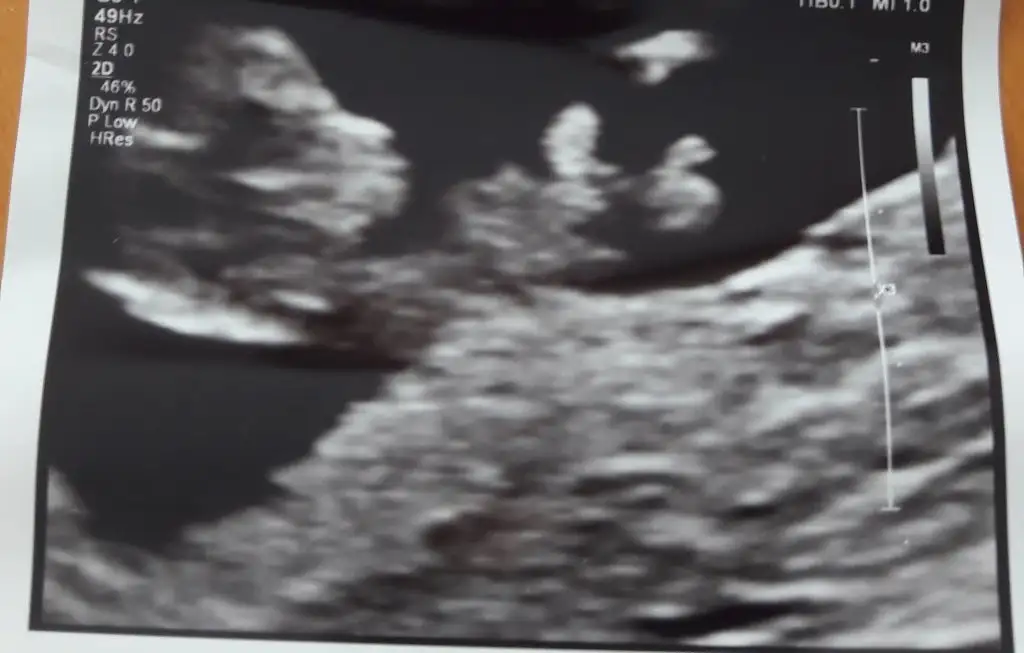

erkek gibi geldi doktorun tahminde bulundumu :)Hayırlı günlerbenimde 12+3 ultrason görüntüm tahminleri alabilirmiyim şimdiden çok teşekkür ederim ❤ Özellikle senden bekliyorum

Nubu görünmüyor başka usg varmı 11 hafta olur varsaHayırlı günlerbenimde 12+3 ultrason görüntüm tahminleri alabilirmiyim şimdiden çok teşekkür ederim ❤ Özellikle senden bekliyorum